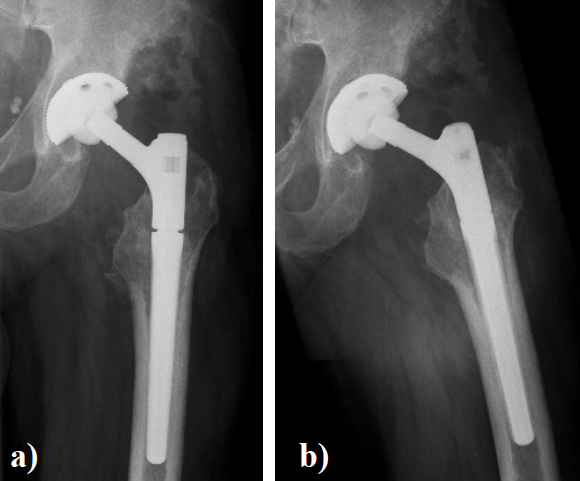

In August 2013 THA was performed due to a girdlestone situation after septic osteoarthritis of the hip (Figure 1) in a 46 year old male patient using a MRP Titan revision stem (Diameter: 18mm, length: 140 mm) (Peter Brehm GmbH, Weisendorf, Germany) and a cementless cup (Allofit - IT; Diameter 54 mm, Zimmer, Warsaw, USA) and a ceramic on ceramic bearing (head diameter: 36 mm) (Figure 2). The patient was 175 cm tall and weighed 105 kg (body mass index: 34.3 Kg/ m2). 2 weeks later revision surgery due to recurrent dislocation (Figure 3) was performed. Revision of the acetabular component was done using an Allofit - Classic- cup, Diameter 56 mm (Zimmer, Warsaw, USA)). The neck component was exchanged from small to medium size (Figure 4). A ceramic on PE bearing was implanted (head diameter: 32 mm). Postoperative healing was uneventful. The patient was out of any complaints. In February 2016 the patient started suffering from slight thigh pain but detected crepitation in the region of the left hip. X-ray of the left hip in 2 planes in May 2016 revealed an asymmetrically gap of the stem / neck junction (Figure 5). During revision surgery of the left hip breakage of the cone of the morse taper junction was visible (Figure 6). Removal of the well-fixed stem was performed via a distal fenestration. After fixation with cerclage wires a bended MRP Titan revision stem (Diameter: 19 mm, Length: 200mm with long neck and extension sleeve) was implanted using a 32 mm ceramic head (Figure 7). Postoperative healing was uneventful.

Figure 7. X - ray of the left hip in 2 planes: ap view a. and lateral; b. view shows revision arthroplasty of the hip using a long bended MRP Titan revision stem with long neck and extension sleeve.